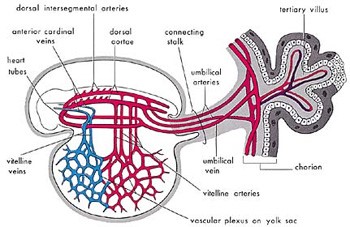

معنی سوم کلمه علقه «لخته شدن خون» است. در این مرحله، ظاهر خارجی جنین و کیسههای آن به دلیل وجود مقادیر نسبتاً زیادی خون شبیه به لخته خون است. [3] (شکل 4 را ببینید). همچنین در این مرحله، خون در جنین تا پایان هفته سوم در گردش نیست. [4] بنابراین، جنین در این مرحله مانند یک لخته خون به نظر میرسد.

شکل 4: نمودار سیستم قلبی عروقی اولیه در یک جنین در مرحله علقه را نشان میدهد